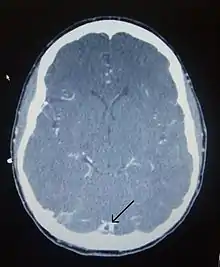

There are various neuroimaging investigations that may detect cerebral sinus thrombosis. Cerebral edema and venous infarction may be apparent on any modality, but for the detection of the thrombus itself, the most commonly used tests are computed tomography (CT) and magnetic resonance imaging (MRI), both using various types of radiocontrast to perform a venogram and visualise the veins around the brain.[2]

Computed tomography, with radiocontrast in the venous phase (CT venography or CTV), has a detection rate that in some regards exceeds that of MRI. The test involves injection into a vein (usually in the arm) of a radioopaque substance, and time is allowed for the bloodstream to carry it to the cerebral veins - at which point the scan is performed. It has a sensitivity of 75-100% (it detects 75-100% of all clots present), and a specificity of 81-100% (it would be incorrectly positive in 0-19%). In the first two weeks, the "empty delta sign" may be observed (in later stages, this sign may disappear).[6]